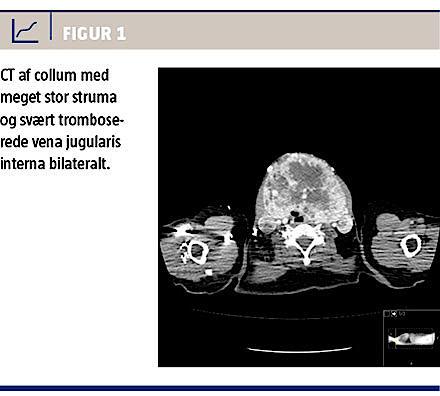

På indlæggelsestidspunktet havde patienten tendens til kvalme og opkastninger, diarréepisoder, ekstreme svedeture, tiltagende træthed, et ikkeintenderet vægttab på 6 kg, tiltagende vækst af struma over seks måneder, kvælningsfornemmelse i rygleje samt 14 dage varende spontant remitterende rødme og smerte på højre side af halsen. Objektivt var hun kronisk medtaget, bleg, havde performancestatus 2, monstrøs struma og fremstående halsvener. Der var anæmi samt forhøjede levertal og C-reaktivt protein-niveau. En CT viste struma på 13 cm i længste mål, svært tromboserede vena jugularis interna bilateralt (Figur 1), metastaselignende forandringer i højre lunge og retroperitoneum og en mindre tumor i højre nyre. En biopsi fra retroperitoneum viste RCC-metastase, og en finnålsaspiration fra glandula thyroidea viste atypiske celler.